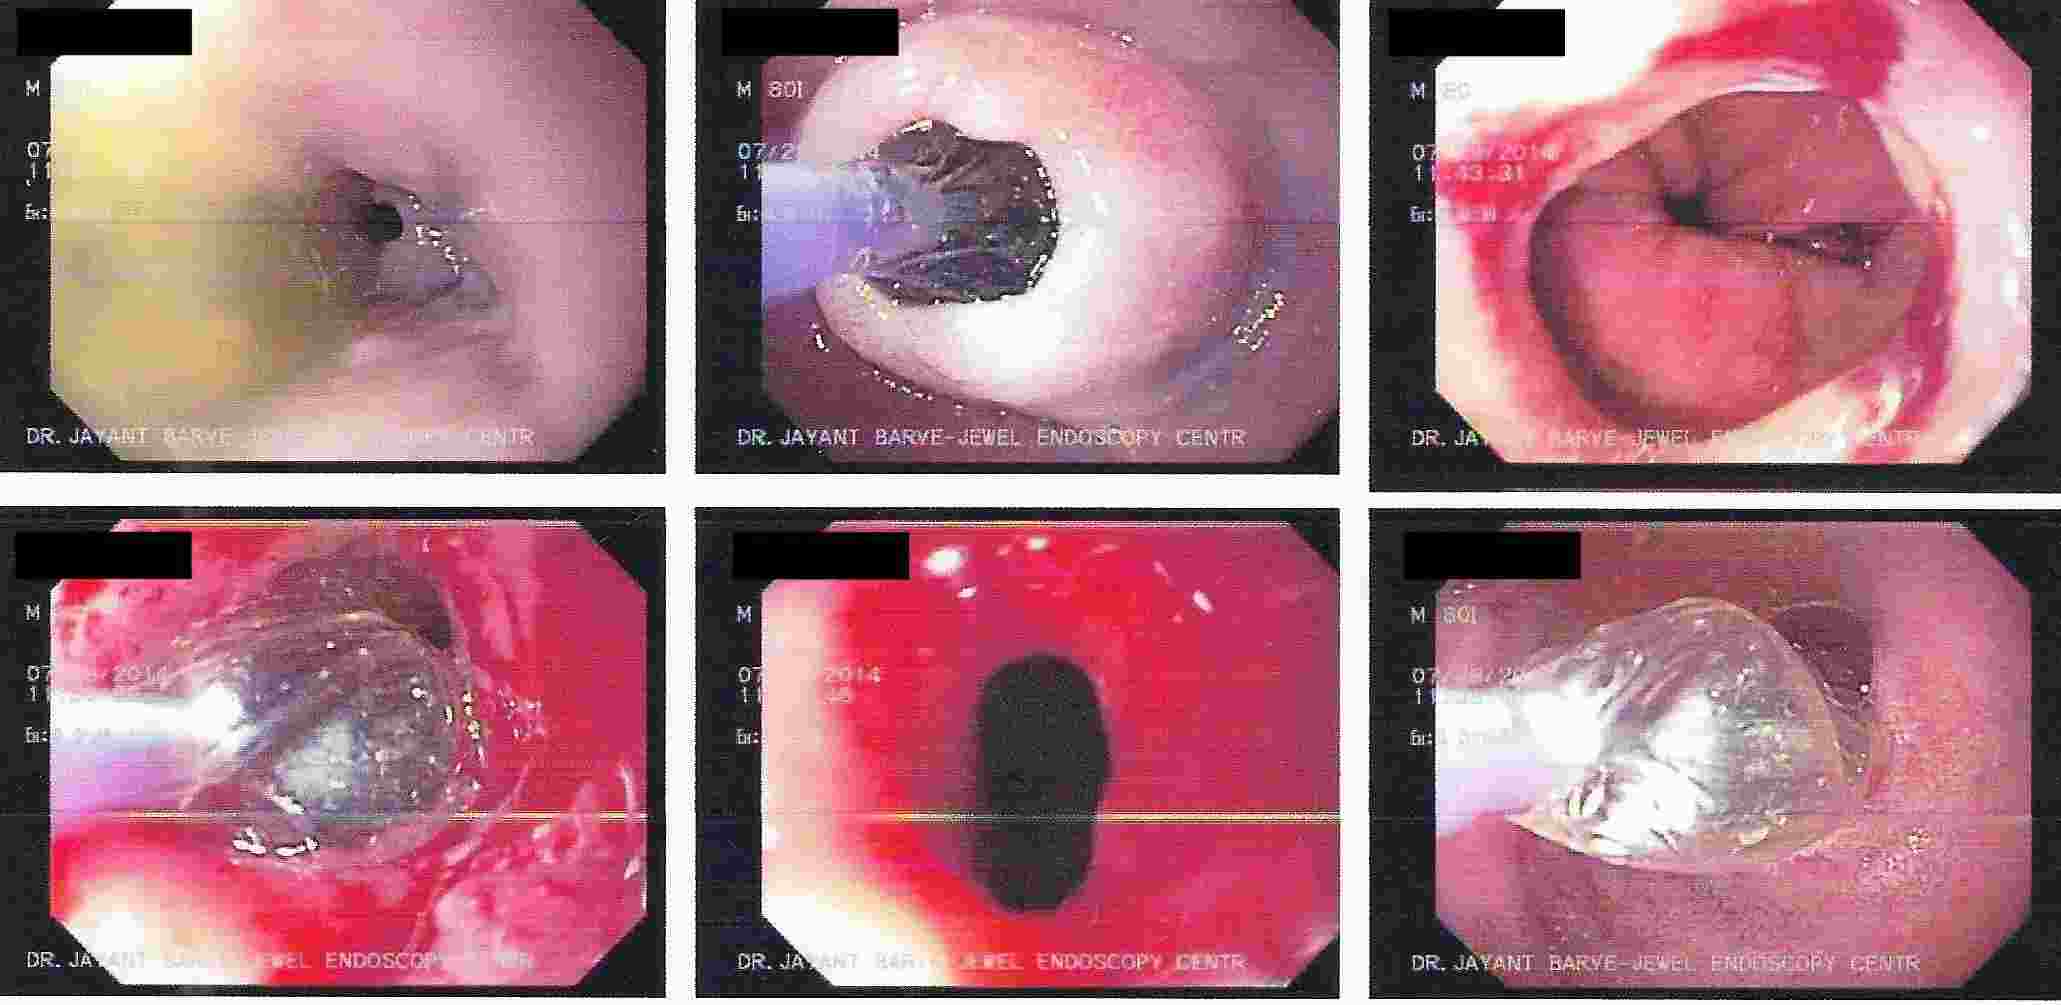

Achalasia Cardia - Balloon Dilatation

Achalasia Cardia - Balloon Dilatation

Achalasia Cardia - Balloon Dilatation

Achalasia Cardia - Balloon Dilatation